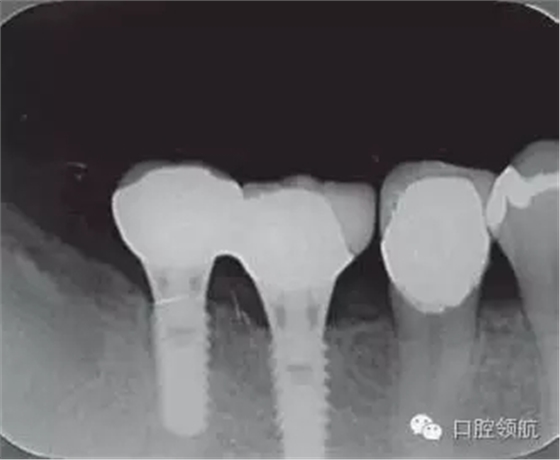

修復體安裝后的2003年1月復診時的X線片上,沒有發(fā)現(xiàn)種植體頸部有骨吸收現(xiàn)象,情況良好(圖2)。但是,2003年8月,因混合陶瓷樹脂部分修復體的破損而進行再制作時,發(fā)現(xiàn)有輕度的咬合疼痛以及舌側頸部的牙齦有輕壓痛。口內沒有觀察到該部位的牙齦紅腫。X線片可以觀察到(左下第6顆牙) 的種植體頸部有達到第4螺紋的骨吸收現(xiàn)象(圖3)。

圖2 沒有發(fā)現(xiàn)種植體頸部的骨吸收(2003年1月)

圖3(左下第6顆牙)的種植體的骨吸收達到第4螺紋(2003年8月)